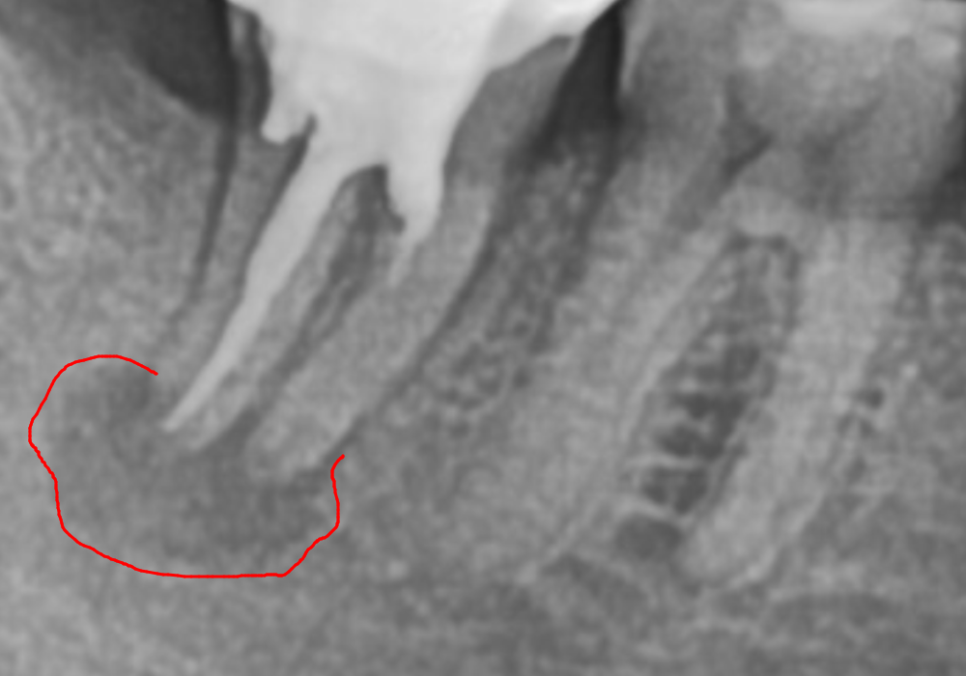

왼쪽 아래 어금니(#36)를 보시면

뿌리 한쪽이 툭 부러져 있는 모습이에요.

241015

부러진 뿌리 위쪽으로 하얗게 보이는 것이

바로 '포스트(Post)'라고 불리는 기둥입니다.

치아 머리가 많이 손상되었을 때

보철물을 지탱하기 위해 심어두는 기둥인데,

그만큼 치아가 약해져 있었다는 뜻이기도 하죠.

결국 딱딱한 음식을 드시다가

뿌리까지 부러져 내원하셨습니다.